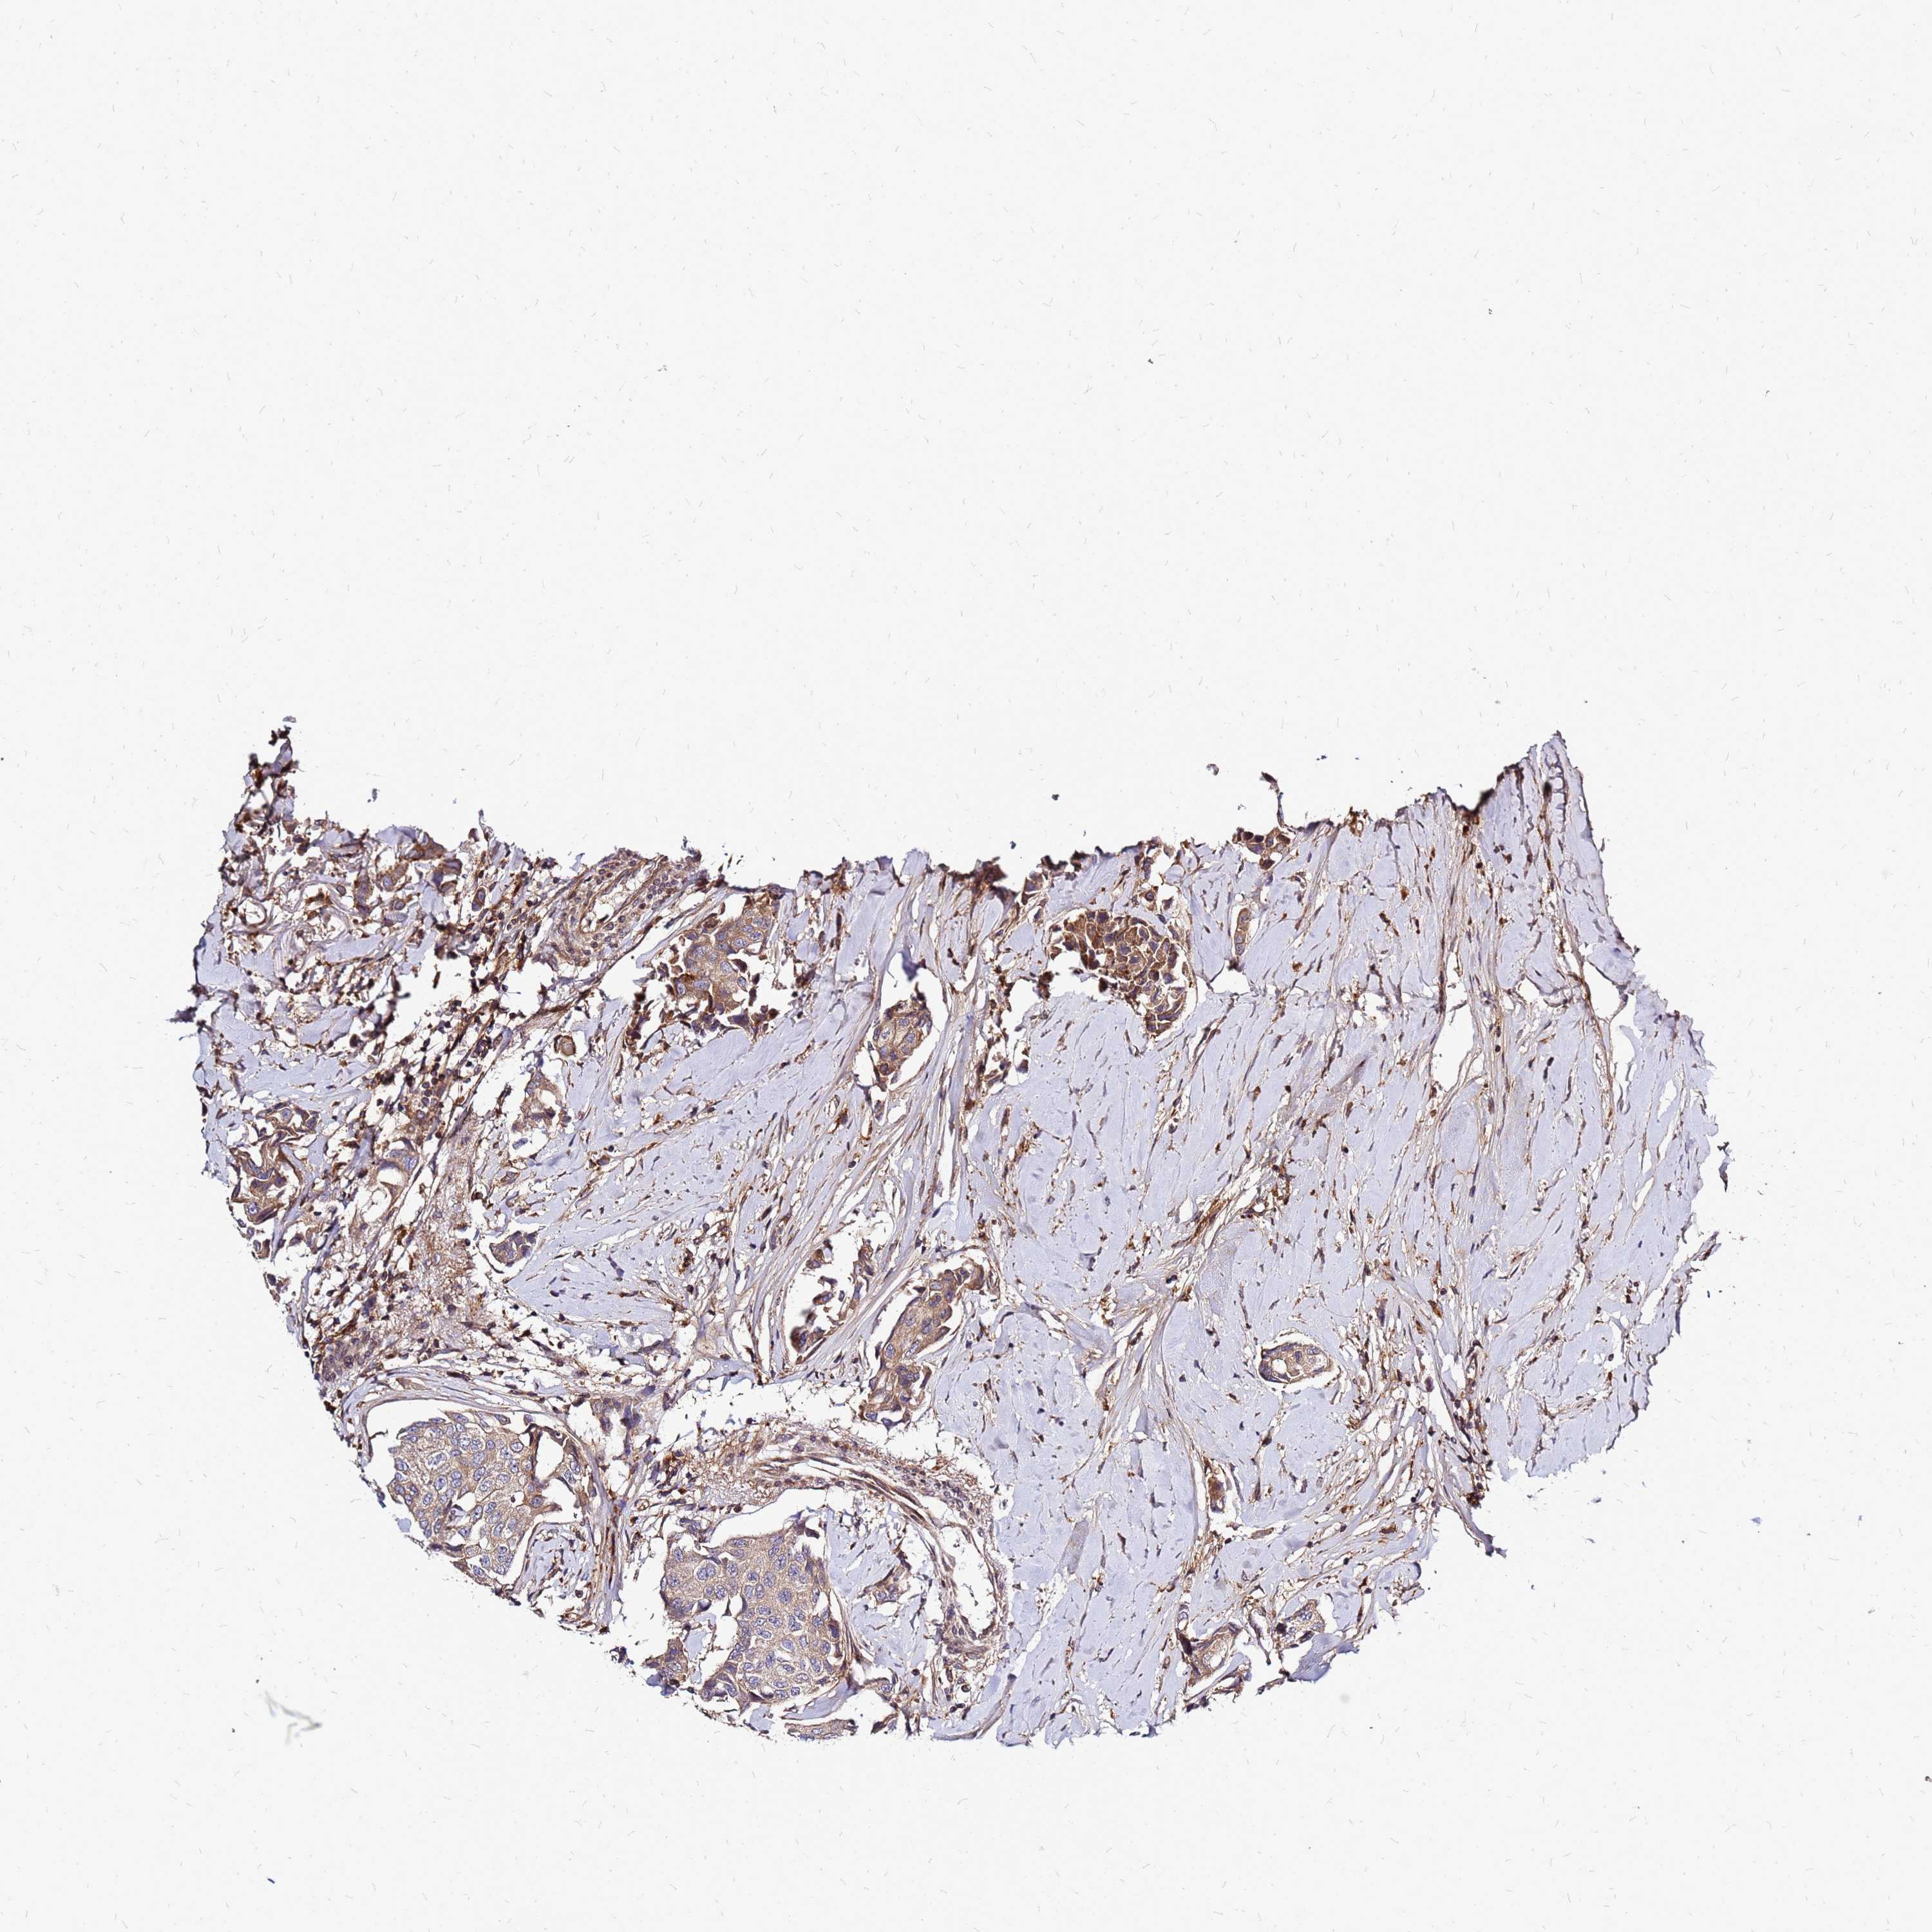

CANCER BREAST CANCER Show tissue menu

BRCA TCGA BRCA VALIDATION PROTEIN EXPRESSION